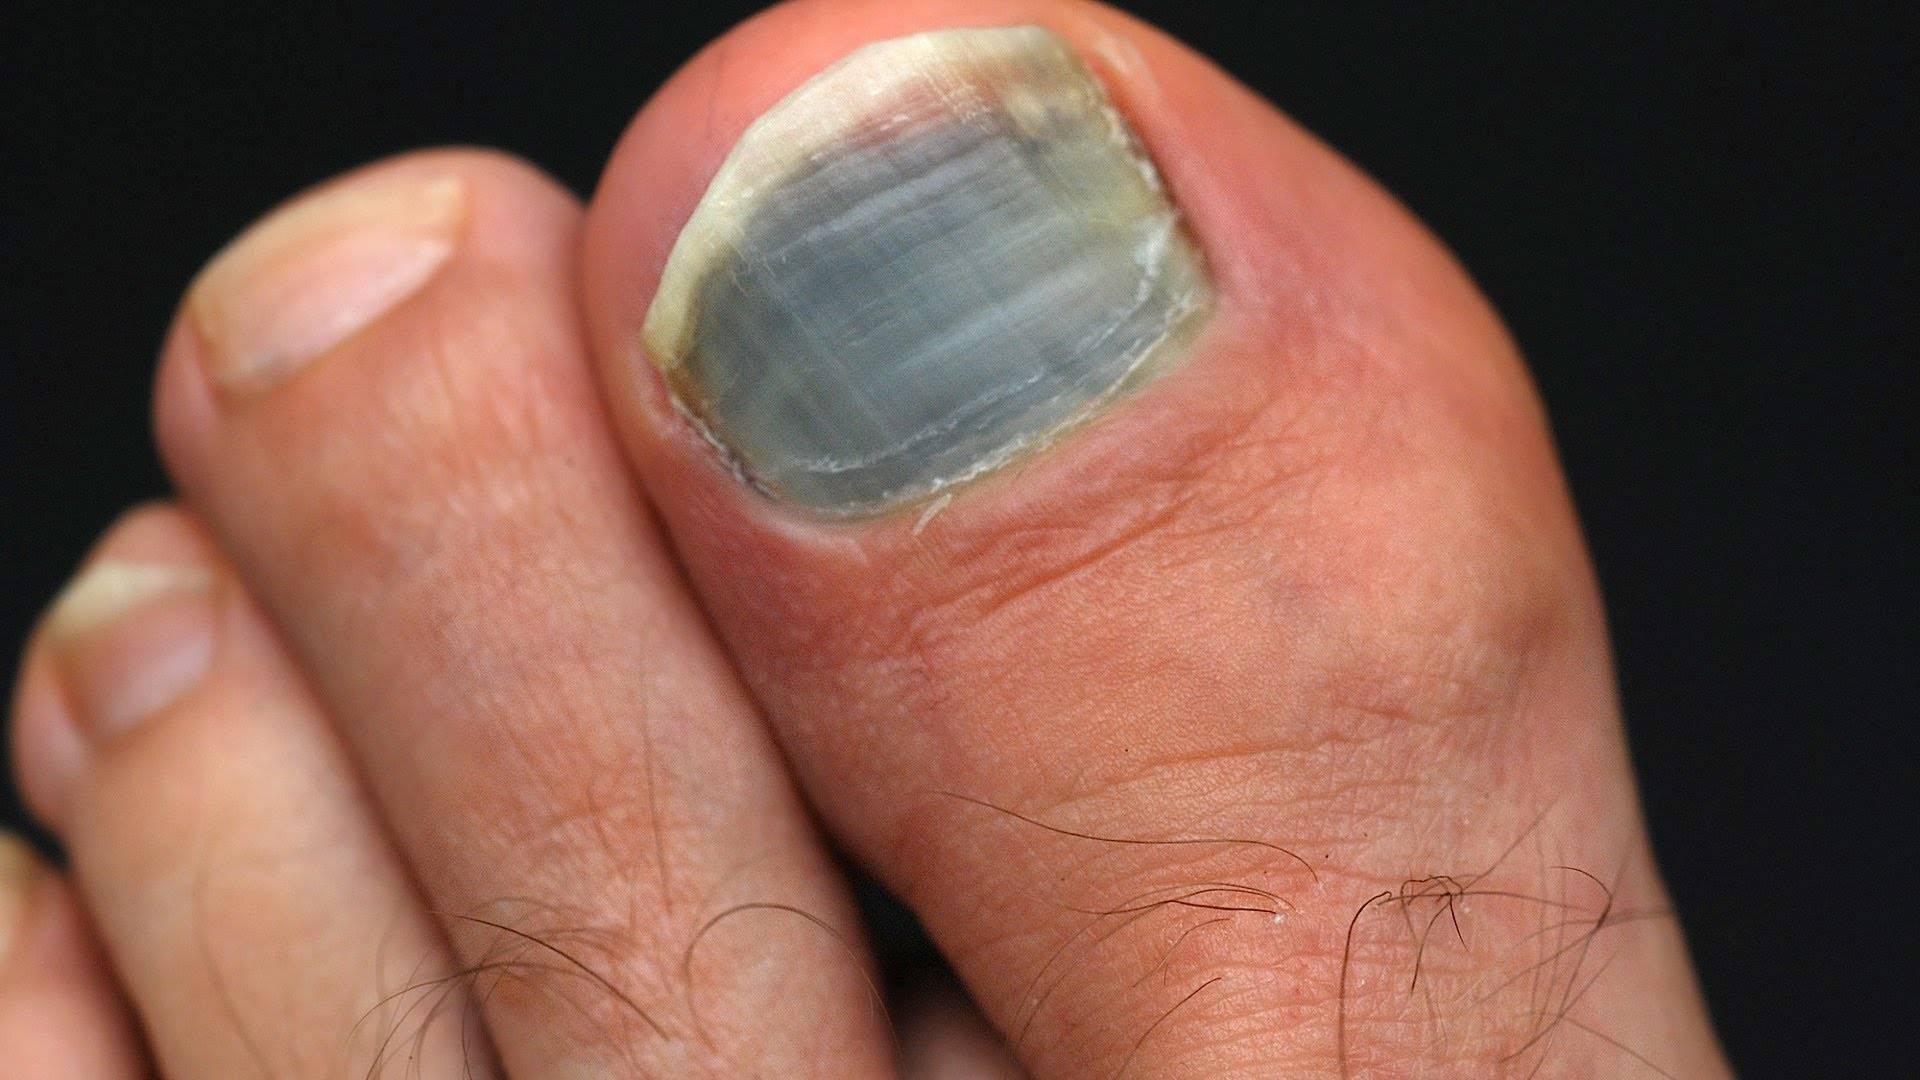

- Травма. В результате повреждения может образоваться гематома (синяк): при ушибе под ногтем нарушается кровообращение, скапливается кровь. Он может занимать его часть или занять всю пластину. При этом возникает сильная пульсирующая боль. Сперва гематома синяя, затем становится черной. Обычно она постепенно уменьшается, и ткани приобретают здоровый оттенок. Ушиб может сопровождаться образованием обломков. Так что в данной ситуации нужно посетить врача, чтобы определить степень травмы и подобрать лечение;

- Причина может скрываться в грибковой инфекции. Недуг можно диагностировать самостоятельно по целому ряду симптомов. В первую очередь страдает кожа, особенно между пальцев. Чаще всего поражаются ноги, а не руки. Постоянный зуд – первый признак грибка, второй симптом – болезненные трещинки между пальцев. Также присутствует шелушение и покраснение. Цвет ногтевых пластин изменяется на желтый, серый, светлый синий и даже черный. Также они теряют прозрачность. Изменяется и структура: появляется ломкость, расслоение, иногда даже сильная деформация. В некоторых случаях пластины могу, наоборот, чрезмерно утолщаться. Если есть подозрения на грибковую инфекцию, нужно обратиться за помощью к врачу-дерматологу;

Абсолютно здоровый человек имеет гладкую ногтевую пластину с равномерным бледно-розовым оттенком без каких-либо вкраплений или полос. Отклонения в цвете или структуре ногтя (смотреть на фото) могут служить сигналом нарушений в работе органов. Но, как мы уже немного разобрались, причина синевы не всегда связана с патологией.

Ногти на ногах чаще синеют по вышеперечисленным или иным причинам, среди которых также выступает посинение вследствие удара. Гематома – распространенная реакция на ушиб, которую врачи определяют без труда.

Но иногда синеет кожа под ногтями пальцев ног и по другим причинами, которые в медицинской практике встречаются также достаточно часто:

- грибок ногтевой пластины. Помимо синего оттенка, болезнь сопровождается рядом других симптомов, таких как деформация ногтей, зуд, слабость пластины, хрупкость ногтевых тканей. В домашних условиях подобную болезнь лечат только после посещения врача, который назначил вам специализированные препараты;

- меланома – злокачественное раковое образование, встречающееся достаточно редко, развивается вследствие повышенного количества пигментных частиц. В большинстве случаев подобная раковая форма проявляется в форме неправильной родинки, и значительно реже растет под ногтями;